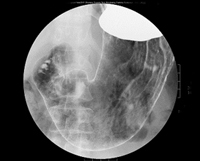

業務内容は胃がん検診が最も多く、その他にも大腸透視や脊髄造影、ERCP(内視鏡的逆行性胆管膵管造影)、イレウス管挿入、整復や気管支鏡生検など多岐に渡ります。